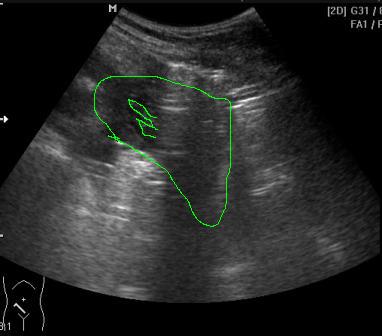

Экстренный - газ в брюшной полости, УЗИ

Пациент с приемного отделения. Жалобы на боль в животе в течение 5 дней.

Перфорация язвы тонкой кишки. Фибринозно-гнойный перитонит.

На снимке жидкость с нитями фибрина (просто не знаю понятно или нет, что я хотела показать).

На снимке гипоэхогенный неоднородный участок клиновидной формы- жидкость в брюшной. В этом месте были линейные эхогенные флотирующие структуры. Что-то и я их на этом снимке уже не могу четко показать (хотя сразу после осмотра мне казалось, что все видно).KsV писал(а): А где здесь нити фибрина? Ткните пальцем в сонограмме, пжл.

Пузырек газа у селезенки на 1 видео и полоса по передней поверхности печени на 2-м(газ смещался при повороте на бок)

У нижнего полюса селезенки есть. Посмотрела снимок на аппарате и вот попыталась обрисовать участок с неоднородной жидкостью и полоски фибрина.KsV писал(а):Пересмотрел еще раз, жтдкости не вижу.

Конечно неполные 4 года практики это мало, но отличить жидкость от тканевого участка, думаю, могу.